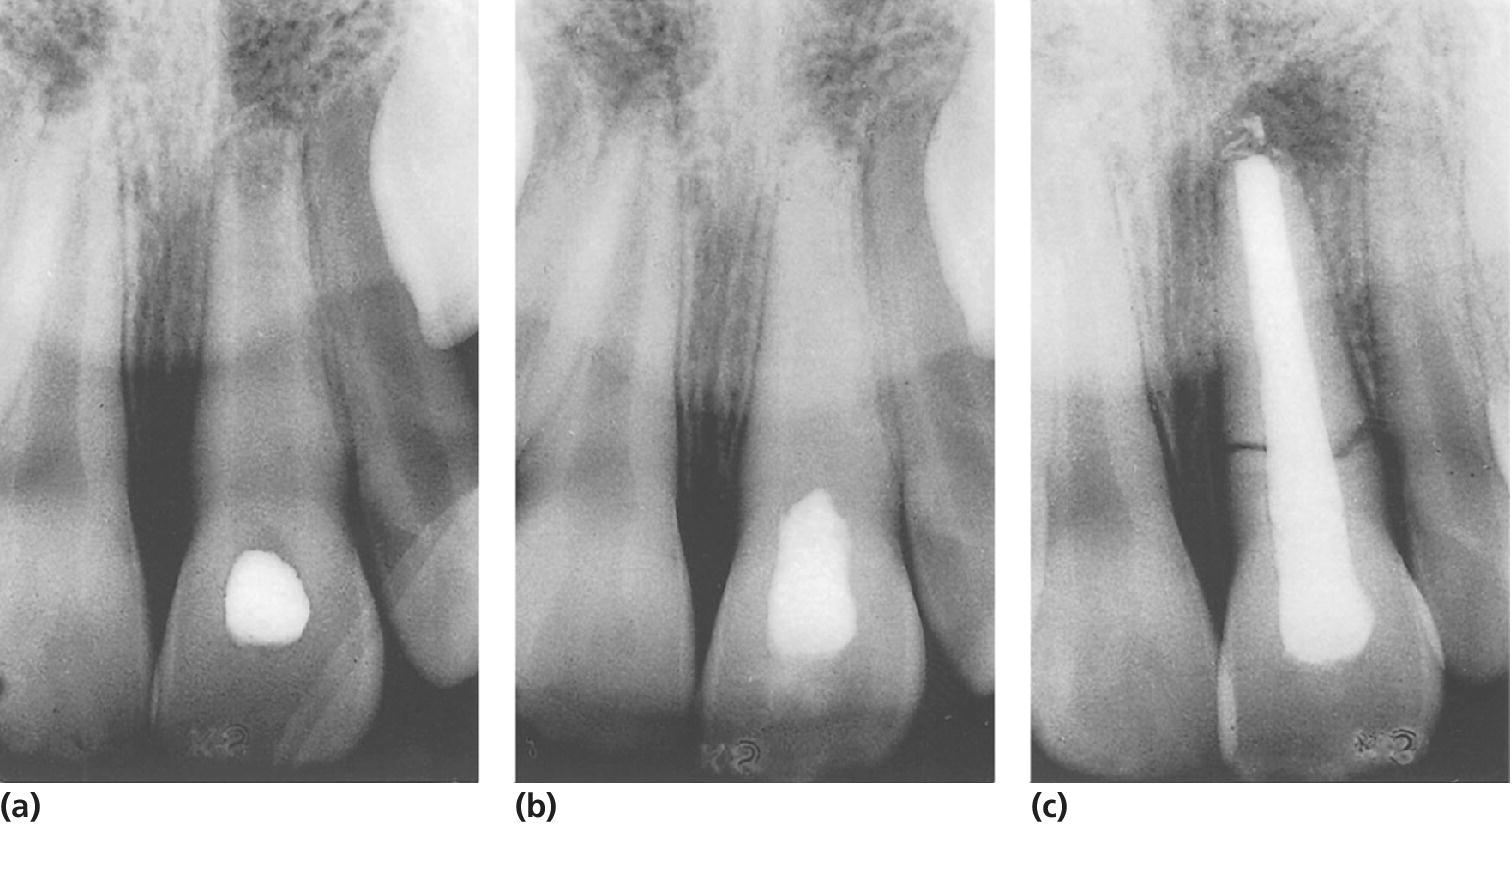

From pocketdentistry.com